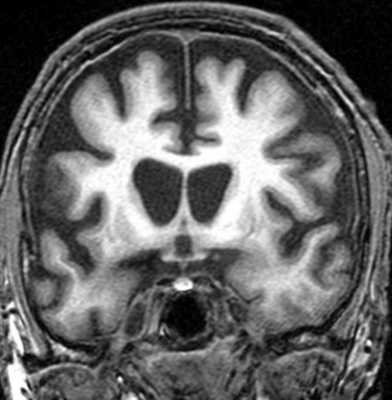

- МРТ головного мозга. Выявляет расширение III желудочка, атрофические изменения среднего мозга, базальных ганглиев, премоторных зон лобной коры и височных областей. Позволяет исключить внутримозговую опухоль, энцефалит, рассеянный склероз, инсульт.

МРТ головного мозга. Т1-взвешенная корональная МРТ. Диффузная атрофия при болезни Альцгеймера.

Синдромы Паркинсона включают группу заболеваний, близких по клинике к болезни Паркинсона. К синдромам Паркинсона относится быстро прогрессирующая деменция с тельцами Леви . При МРТ головного мозга низкий сигнал наблюдается не только от компактной части черного вещества, но и от скорлупы, которая становится даже темнее бледного шара. При оливопонтоцеребеллярной атрофии на сагиттальных МРТ головного мозга видно уменьшение объема моста и мозжечка. При прогрессирующем надъядерном параличе обнаруживается атрофия пластины четверохолмия. Описаны характерные симптомы при МРТ - «пингвина», «Микки Мауса» и другие, смысл которых заключается в описании признаков атрофии.